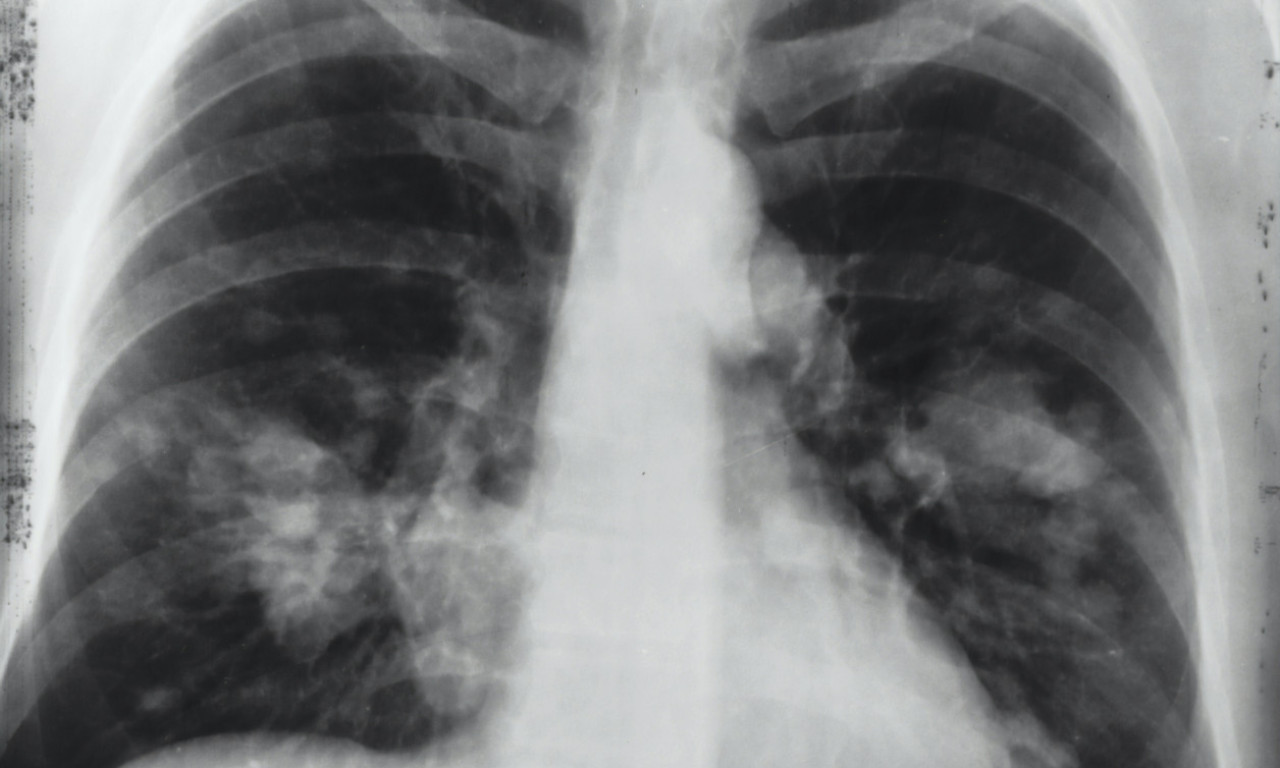

SrbijaRak pluća je vodeći uzrok smrti od raka u svetu, a godišnje ima 1,8 miliona smrtnih slučajeva od kancera pluća

Rak pluća je vodeći uzrok smrti od raka u svetu, a godišnje ima 1,8 miliona smrtnih slučajeva od kancera pluća.